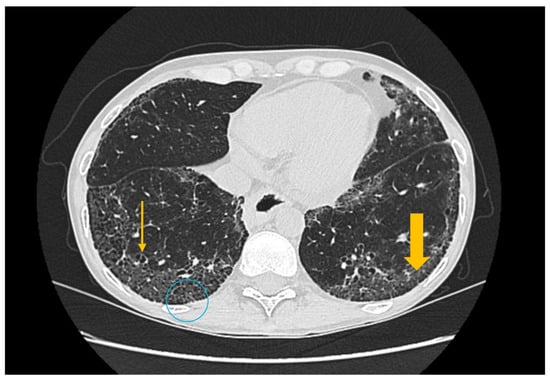

The Role of Imaging Techniques in the Evaluation of Extraglandular Manifestations in Patients with Sjögren’s Syndrome

Sjögren’s syndrome is a chronic autoimmune disease marked by lymphocytic infiltration of the exocrine glands and the development of sicca symptoms, yet some patients also develop extraglandular involvement. Imaging has become relevant for describing these systemic features and supporting clinical assessment. This review discusses the roles of ultrasonography, elastography, computed tomography, and magnetic resonance imaging in evaluating multisystem disease associated with Sjögren’s syndrome. Ultrasonography and elastography help assess muscular involvement by showing changes in echogenicity and stiffness that reflect inflammation and later tissue remodeling. In joints, ultrasound can detect synovitis, tenosynovitis, and early erosive changes, including abnormalities not yet evident on examination. Pulmonary disease, most often with interstitial lung involvement, is best evaluated with high-resolution computed tomography, which remains the most reliable imaging modality for distinguishing interstitial patterns. Magnetic resonance imaging is valuable in assessing neurological complications. It can reveal ischemic and demyelinating lesions, neuromyelitis optica spectrum features, or pseudotumoral appearances. Imaging is also essential for detecting lymphoproliferative complications, for which ultrasound and magnetic resonance imaging can reveal characteristic structural and diffusion-weighted imaging findings. When combined with clinical and laboratory information, these imaging methods improve early recognition of systemic involvement and support accurate monitoring of disease progression in Sjögren’s syndrome. Full article